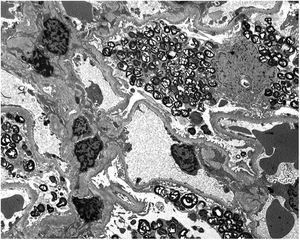

Renal biopsy results show (Fig. 1) increased focal and segmental mesangial matrix with increased cellularity. Both endothelial and epithelial cells show large, multivacuolar cytoplasm. Tubular foam cells are also seen. No interstitial or vascular involvement was identified. Electron microscopy (Fig. 2) shows a massive number of myelin-like inclusions predominantly located within podocytes, with a minimal proportion of such inclusions in endothelial, mesangial and tubular cells. The results lead us to the diagnosis of FD and it was decided to start enzyme replacement therapy (ERT) with agalsidase beta and angiotensin-converting enzyme inhibitors (ACE inhibitors).